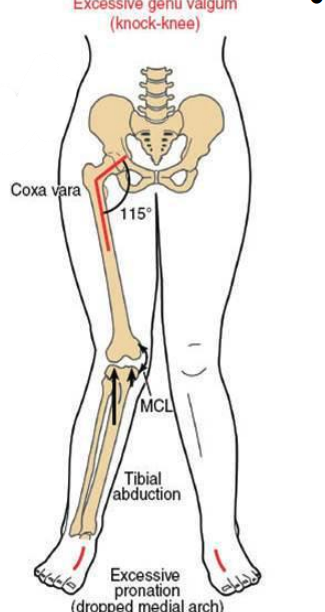

Clinical implications of coxa valga

-angle of inclination is > normal

-decreases abduction moment arm leading functionally weakened hip and increased joint reaction force

-decreased stability due to lessened coverage of the femoral articular surface with the acetabulum

-prediposes to hip dislocation

LE chain effects of coxa valga

-less stability

-shallow acetabulum

-abducted hip

-genu varum at the knee

-supination of the foot

-longer limb

clinical implications of coxa vara

-increased hip joint stability

-increases moment arm of abductors (functionally stronger hip) reduces joint reaction force

-increase bending moment across femoral neck predisposition for (slipped capital femoral epiphysis or femoral neck fracture)

LE Chain effect of Coxa Vara

increased shear force across the femoral neck, adducted hip, valgus knee, pronation at foot, shorter limb